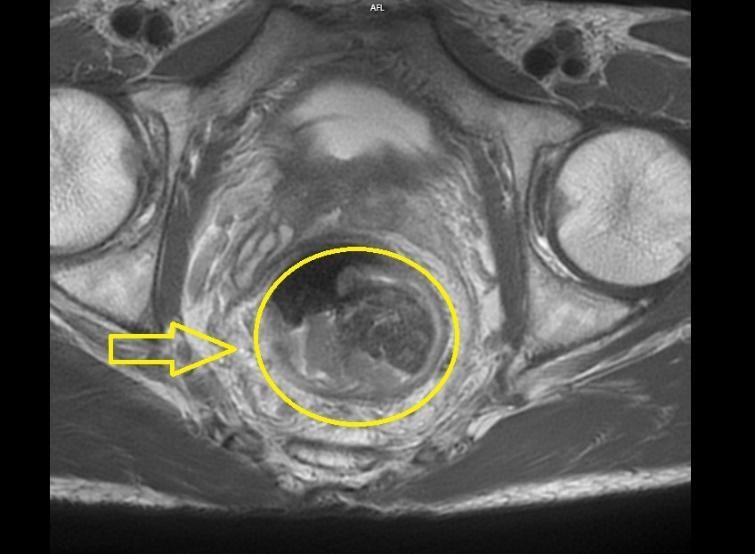

Chụp MRI ổ bụng và tiểu khung:

![]() |

Hình 2: Hình chụp MRI

Hình ảnh khối u cách rìa hậu môn 80mm, trên đoạn dài 50mm. Khối u ôm quanh thành trực tràng, dày không đều quanh chu vi gây chít hẹp lòng ruột, chỗ dày nhất ở 6h-9h (18mm). Tổn thương có xâm lấn lớp cơ trực tràng, có lan đến tổ chức mỡ ngoài thành trực tràng cách > 1mm.